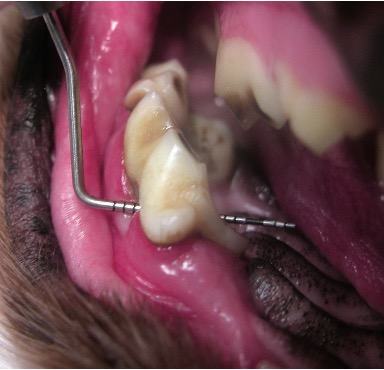

Diagnostic Standards as the Foundation of Effective Treatment